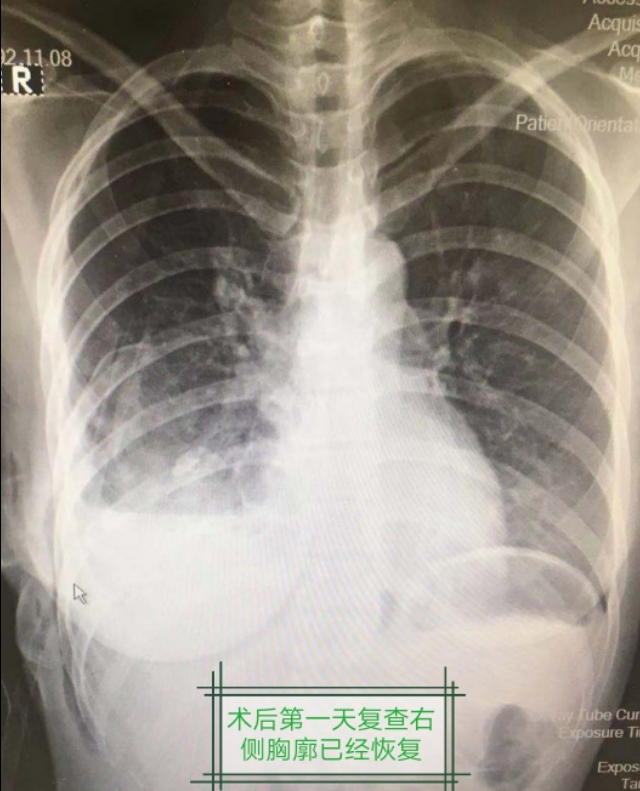

手术顺利,康复顺利也是必须滴……

手术后第五天顺利康复出院……术后第八天回院拆线,小姑娘已经满血复活了������������������������

高兴的向我们汇报:手术前我深呼吸受限,胸部像带着紧箍咒一样,肩膀也是斜的,脊柱是弯的,手术后回家对时候家里人惊讶的发现,我的两肩一边高了,脊柱也直了!我现在是真轻松了!期待再次复查,继续给她惊喜……这就是现代科技进步给病人带来的实实在在的福利。